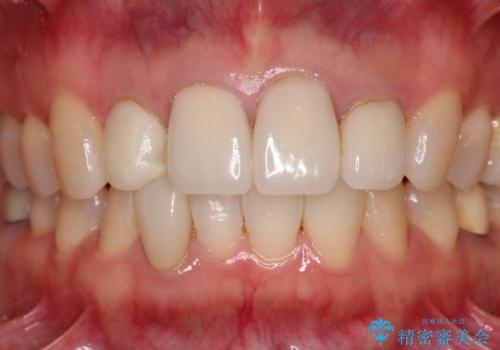

欠けてしまったセラミッククラウン 周囲のクラウンと同様の色彩で再製作

- 上顎4前歯に装着されているセラミッククラウンのうち、ひとつが欠けてしまったとのことで来院された患者様です。

土台となっている歯には問題がないため、周囲のセラミッククラウンと色調が合うように、オーダーメイドタイプのセラミッククラウンにて補綴治療を行うこととしました.

欠けてしまったセラミッククラウンはガラス系セラミッククラウンであったため、今回製作する歯は、強度の強いジルコニアセラミッククラウンとしました。

クラウンの種類は異なりますが、色調の適合したクラウンを装着することができました。